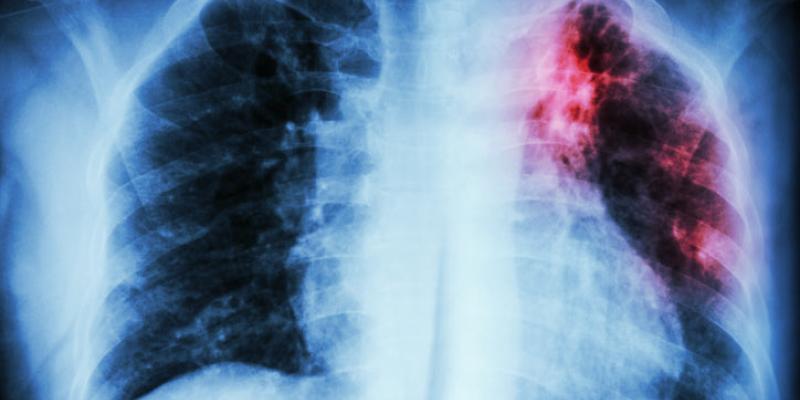

Esta enfermedad, lejos de ser erradicada, es una de las primeras causas de origen infeccioso en el mundo. Según la Organización Mundial de la Salud (OMS), se trata de una patología provocada por una bacteria que afecta, en la mayoría de los casos, a los pulmones.

Como puede ocurrir con la Covid-19, la tuberculosis se transmite de persona a persona, a través del aire. Cuando un afectado por la enfermedad pulmonar tose, estornuda o escupe, expulsa gérmenes tuberculosos al aire. Basta con que una persona inhale unos pocos para quedar infectada.

La Covid-19 y la tuberculosis son enfermedades “parecidas” desde el punto de vista del manejo clínico. Según los expertos, ambas pueden convivir y son difíciles de diferenciar porque tienen síntomas comunes, como tos, fiebre y disnea.